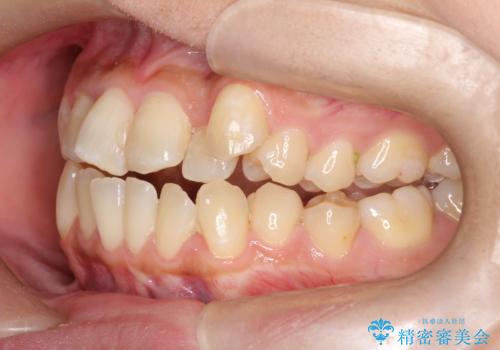

- 患者様は左上の八重歯を気にされて来院されました。八重歯による歯列の乱れだけでなく、翼状捻転(歯がねじれるように生えている状態)も見られました。目立たない矯正を希望されていたため、**インビザライン(マウスピース矯正)**を選択し、左上の小臼歯を抜歯してスペースを作りながら歯を並べる治療計画を立てました。しかし、治療の途中で翼状捻転の改善が十分に進まなかったため、患者様の希望も踏まえ、上顎のみワイヤー矯正に変更することとなりました。

治療開始時はインビザラインを使用し、全体の歯並びを整えながら抜歯スペースを活用して歯を後方へ移動させました。しかし、左上の八重歯のねじれが強く、マウスピースのみでは十分にコントロールできないことが判明。そこで、より細かく歯を動かすために上顎のみワイヤー矯正へ切り替えました。ワイヤー矯正によって翼状捻転も改善し、最終的にバランスの取れた歯並びと噛み合わせを実現。患者様からは「長い治療だったけれど、しっかり整って満足」と嬉しいお言葉をいただきました。